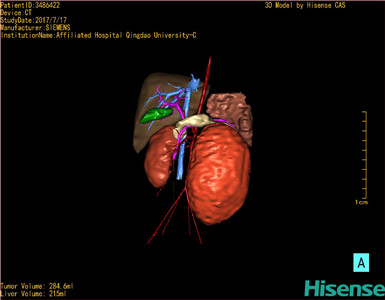

肾母细胞瘤-CH-001-N-001503

CT结果输入海信CAS系统后行3D重建及手术规划后,于2017-7-21全麻下行“左肾切除术”手术治疗:

术前三维重建及手术方案设计:

将0.625mm双源薄层CT资料的静脉期和动脉期Dicom格式文件导入海信CAS系统。

通过调节窗宽窗位调整CT序号,对肿瘤,肝实质,胆囊,下腔静脉,肿瘤,肝动脉、门静脉及肝静脉等进行三维重建;系统自动计算肿瘤体积和肝脏体积。

模拟手术操作,自动计算切除肿瘤体积。肝脏体积为215ml,肾脏肿瘤大小为284.6ml通过术前模拟手术,精准判断手术可行性。

术前三维重建:

重建图片